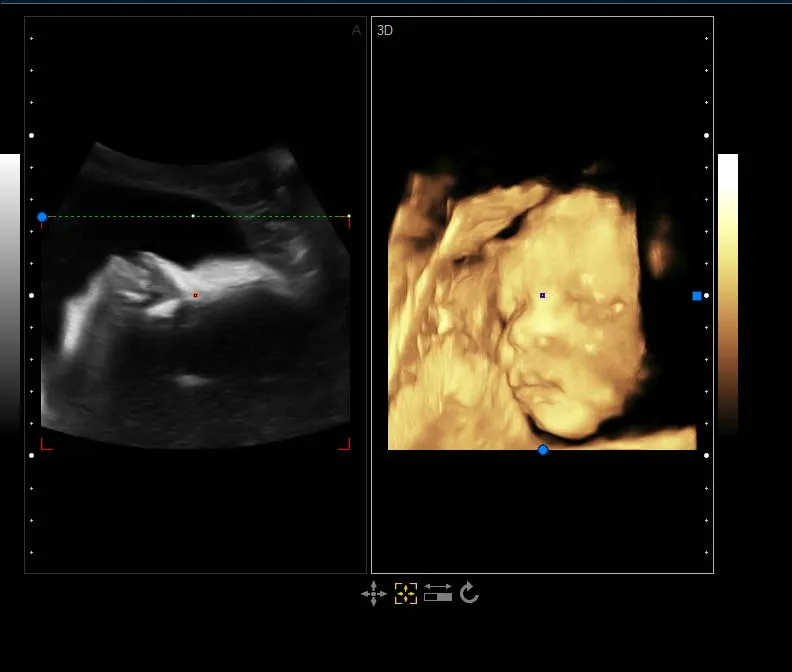

Standard Configuration | Main Unit 3.5Mhz convex probe 4D Volume probe and software 19'LED display with 10.4’ touch screen CW function ( work with phased array probe) USB ports, DICOM 3.0,DVD-RW |

Professional measurement software packages | Obstetric measurement Andrology measurement Gynecological measurement Urology measurement Peripheral vascular measurement Multiple births measurement Small organ measurement Orthopedic measurement Cardiac measurement |